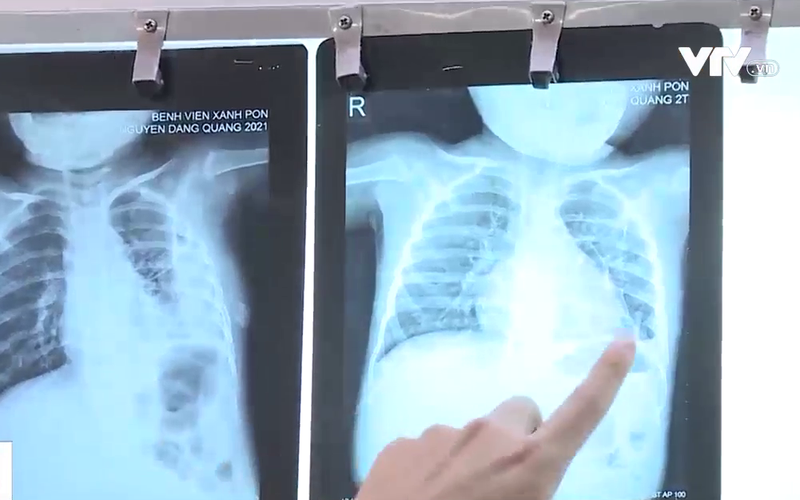

Bệnh nhi này vừa trải qua cơn nguy kịch sau gần 1 tháng điều trị viêm phổi do tụ cầu. Đáng nói trước đó, bé sốt khoảng chục ngày nhưng gia đình vẫn không phát hiện ra bệnh. Chỉ từ nốt nhọt ở gót chân, bệnh nhi xuất hiện tình trạng áp xe phổi, viêm màng phổi.

Chị Đỗ Thảo Ly, TP. Hà Nội cho biết: “Chụp phim đã bị mưng mủ trắng hết bên phổi rồi. Chỉ có 2 nốt thôi rất to nên không biết cách điều trị như nào”.

TS.BS. Phan Thị Kim Dung – Phó trưởng khoa Nhi hô hấp, Bệnh viện Đa khoa Xanh Pôn cho biết: “Sẽ tìm thấy những ổ trên da, mụn nhọt do tụ cầu, sau đó trẻ mới có những biểu hiện về hô hấp. Trên da mà có ban hay nhọt như thế, đôi khi cha mẹ không đi khám bệnh thì dễ nhầm lẫn vấn đề liên quan đến virus như chân tay miệng hay ban khác mà đôi khi họ ko biết tưởng là sốt xuất huyết”.